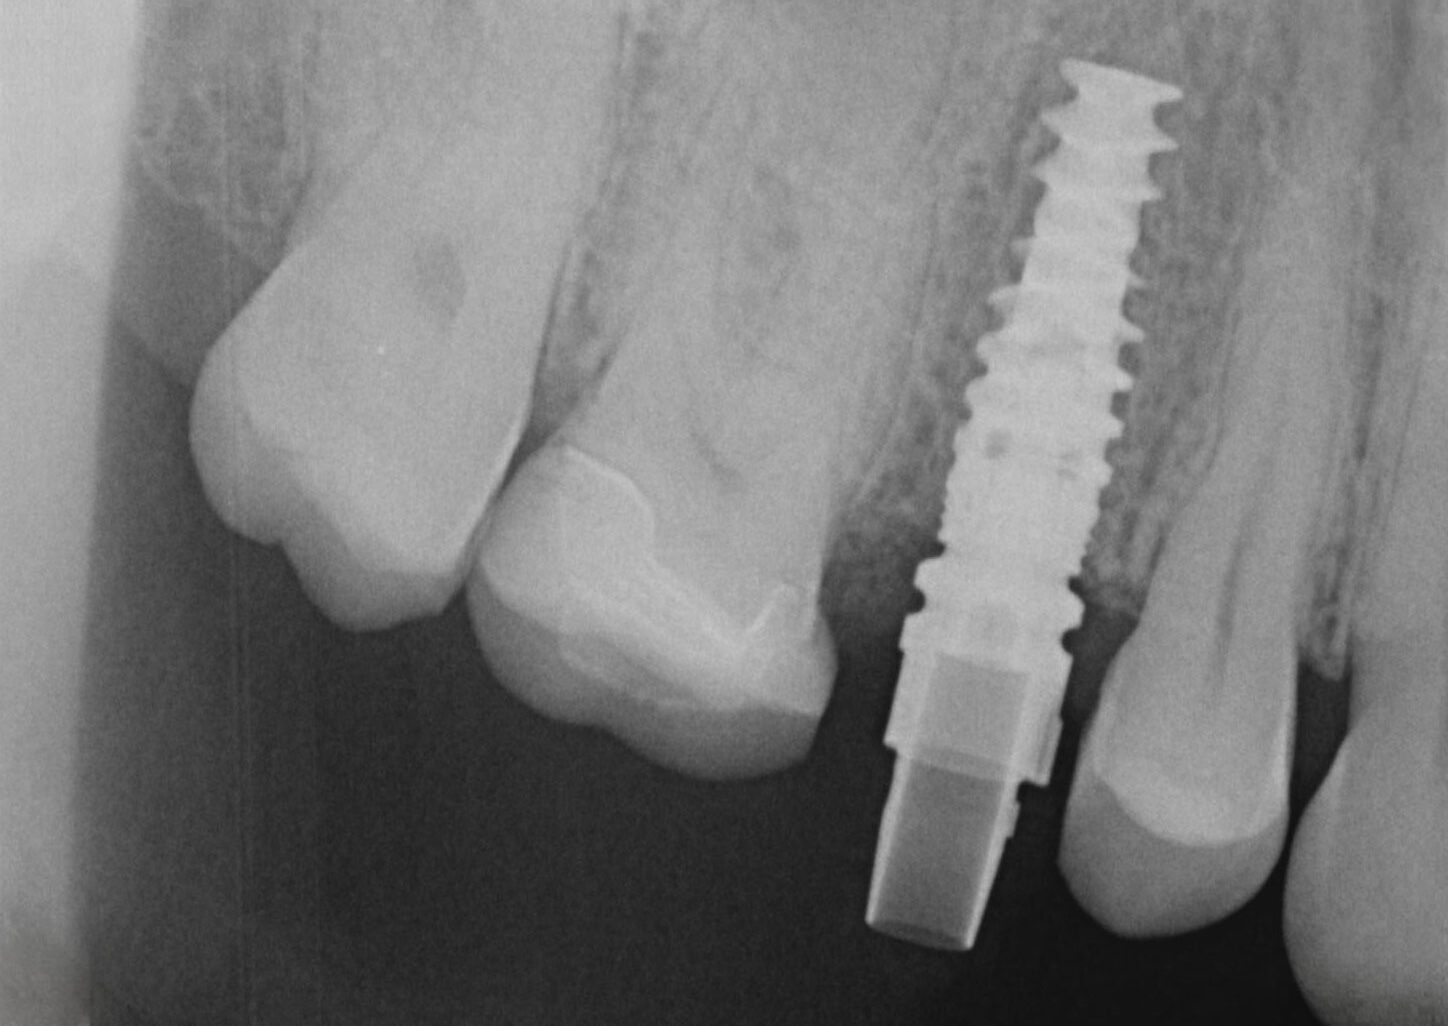

IMPLANTOLOGIE

Ein Zahnimplantat wird im Kieferknochen verankert und übernimmt damit die Funktion einer Zahnwurzel. Das Implantat ermöglicht den festsitzenden oder herausnehmbaren Zahnersatz bei Zahnverlust, wobei der Komfort im Vergleich zu herkömmlichen Varianten erheblich gesteigert wird. Der Eingriff erfolgt unter örtlicher Betäubung.

Mit Hilfe moderner digitaler Implantationsplanung lässt sich im Vorfeld der OP die ideale Implantatgröße und -position im Kiefer festlegen. Der Ablauf der Implantation kann dadurch vereinfacht und Risiken minimiert werden.

Bei entsprechender Pflege und regelmäßiger professioneller Nachsorge durch uns ist ein Verlust von Implantaten nicht zu erwarten.